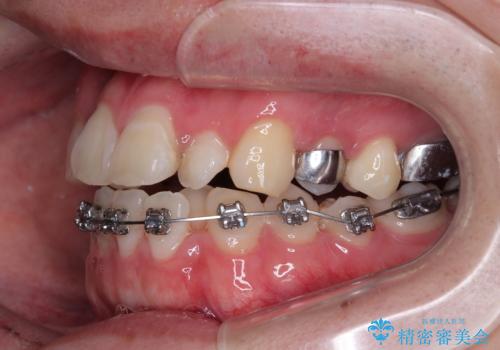

治療方針

このような歯列の狭さに起因するデコボコを改善するために、**MARPE(骨に固定する上顎急速拡大装置)**を使用して、上顎の横幅を拡大し、これにより歯が並ぶためのスペースを確保し、メタルブラケットを用いて歯列を整えていく計画としました。

費用面を考慮し、装置はコストパフォーマンスに優れたメタルブラケットを選択。見た目よりも機能と効果を重視したい方には特におすすめの選択肢です。